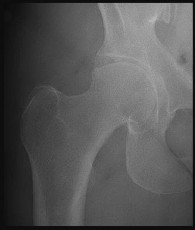

Question 39:

A 38-year-old male presents with right hip pain. He has a history of long-term corticosteroid use for severe asthma. Radiographs demonstrate an area of sclerosis and subchondral radiolucency (crescent sign) in the anterosuperior aspect of the femoral head, consistent with osteonecrosis. According to the modified Ficat and Arlet classification, the presence of a structural subchondral collapse (crescent sign) without narrowing of the hip joint space places him in which stage?

Correct Answer: Stage III

Explanation:

The Ficat and Arlet classification is classically used to stage osteonecrosis of the femoral head based on standard radiographs. Stage I has normal radiographs (but positive MRI). Stage II shows cystic/sclerotic changes without subchondral collapse. Stage III is defined by subchondral collapse, which is classically visualized as the 'crescent sign' (subchondral radiolucency indicating mechanical failure of the trabecular bone), but the joint space remains preserved. Stage IV involves secondary osteoarthritis with joint space narrowing and acetabular changes.